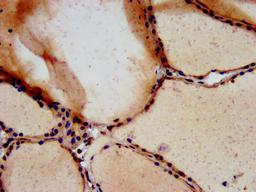

IHC image of CSB-PA025167LA01HU diluted at 1:700 and staining in paraffin-embedded human thyroid tissue performed on a Leica BondTM system. After dewaxing and hydration, antigen retrieval was mediated by high pressure in a citrate buffer (pH 6.0). Section was blocked with 10% normal goat serum 30min at RT. Then primary antibody (1% BSA) was incubated at 4°C overnight. The primary is detected by a biotinylated secondary antibody and visualized using an HRP conjugated SP system.